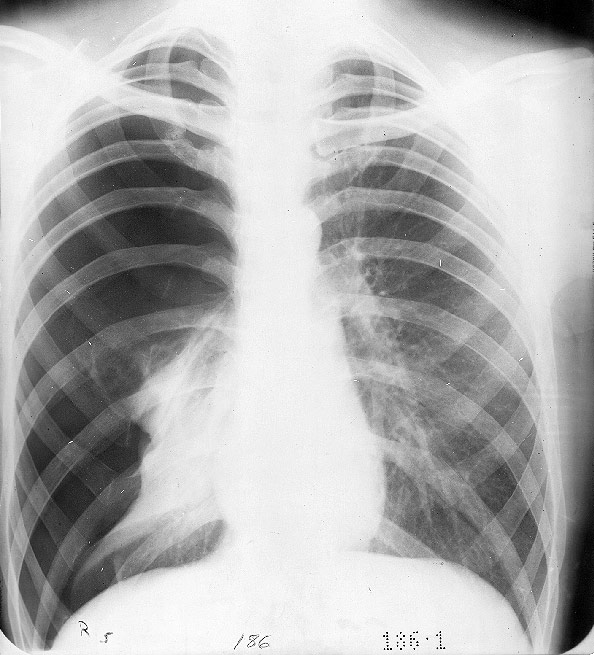

Ocasionalmente, la fisura por donde penetra el aire se comporta como una válvula que permite la entrada de aire a la pleura en cada inspiración, pero no su salida. Con ello, la presión intrapleural se va haciendo progresivamente positiva con colapso total del pulmón ipsilateral y, si no se corrige rápidamente provoca desviación del mediastino y colapso del pulmón contralateral. La placa 47 corresponde a un neumotórax derecho a presión en el cual el pulmón de ese lado está colapsado totalmente hacia el hilio y el mediastino se está desplazando hacia la izquierda.